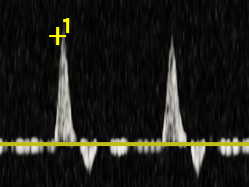

Doppler żył-prawidłowe przepływy.